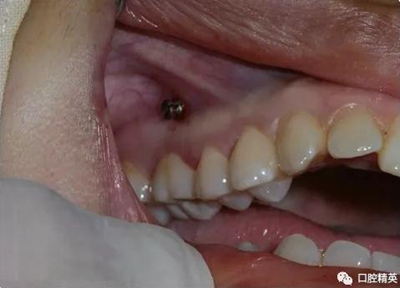

上頜種植釘?shù)闹睆?.6,長度11mm;下頜直徑2.0,長度9mm

1、上頜種植釘常見位置在5,6之間;下頜種植釘常見位置在6,7之間。

2、助攻型種植釘,上頜與頜骨成30-40°角,下頜與頜骨成10-20°角(目的:1、降低損傷牙根及牙周膜的機(jī)率;2、使種植釘盡量植入骨皮質(zhì)內(nèi),降低松動(dòng)機(jī)率);自攻型種植釘與頜骨垂直;個(gè)人習(xí)慣:自攻型種植釘上下頜均與頜骨成30-40°角。